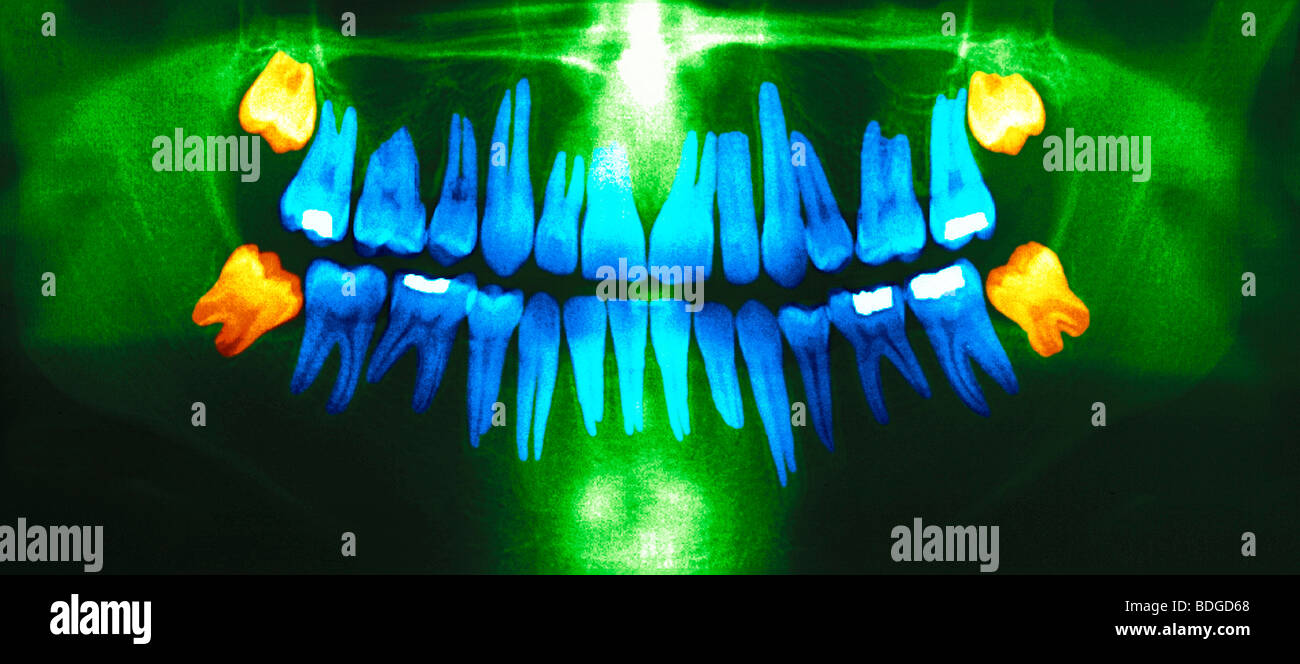

Wisdom Teeth Eruption, Panoral X-ray - Stock Image - C013/1068

Panoramic Dental X-ray With Superior Upper Wisdom Tooth (eight Tooth

www.alamy.comtooth

www.alamy.comtooth